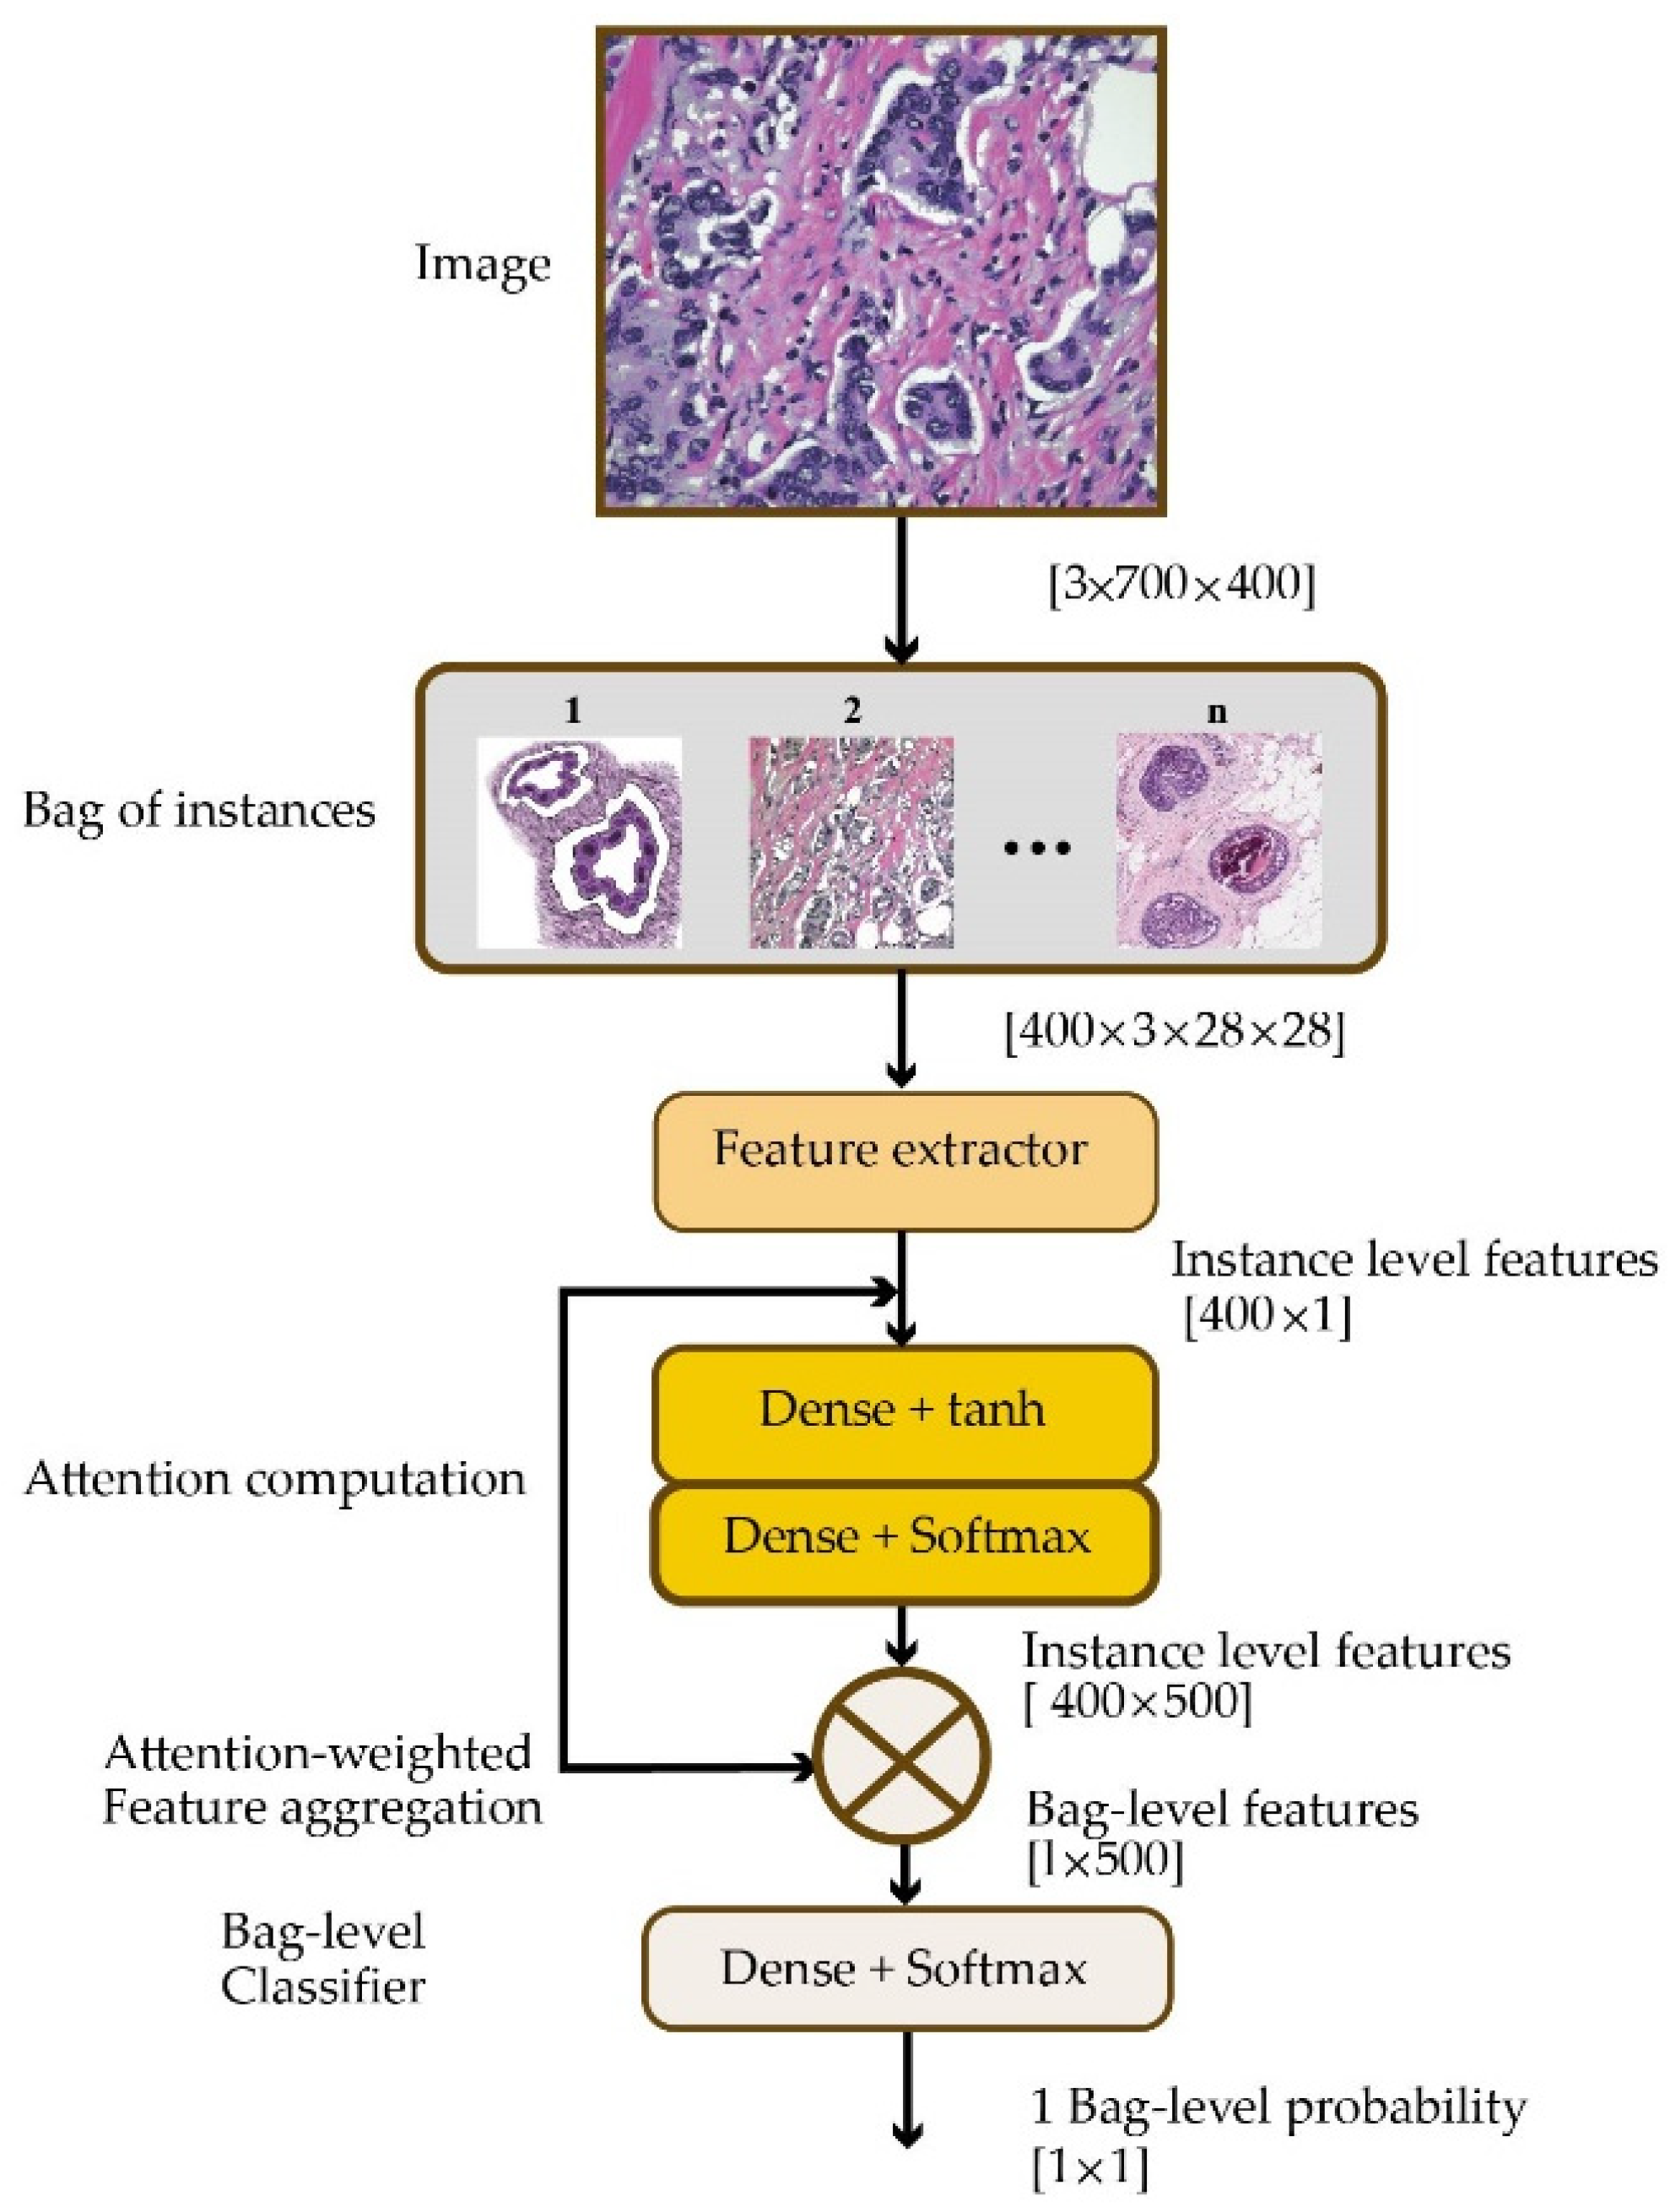

Data That Shows Early Detection Rather Than Late Detection In Breast Cancer

Build inspiration with our stunning architectural Data That Shows Early Detection Rather Than Late Detection In Breast Cancer collection of extensive collections of structural images. structurally highlighting photography, images, and pictures. perfect for architectural portfolios and presentations. Our Data That Shows Early Detection Rather Than Late Detection In Breast Cancer collection features high-quality images with excellent detail and clarity. Suitable for various applications including web design, social media, personal projects, and digital content creation All Data That Shows Early Detection Rather Than Late Detection In Breast Cancer images are available in high resolution with professional-grade quality, optimized for both digital and print applications, and include comprehensive metadata for easy organization and usage. Discover the perfect Data That Shows Early Detection Rather Than Late Detection In Breast Cancer images to enhance your visual communication needs. Cost-effective licensing makes professional Data That Shows Early Detection Rather Than Late Detection In Breast Cancer photography accessible to all budgets. The Data That Shows Early Detection Rather Than Late Detection In Breast Cancer archive serves professionals, educators, and creatives across diverse industries. Time-saving browsing features help users locate ideal Data That Shows Early Detection Rather Than Late Detection In Breast Cancer images quickly. Each image in our Data That Shows Early Detection Rather Than Late Detection In Breast Cancer gallery undergoes rigorous quality assessment before inclusion.